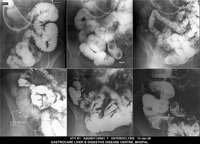

Section: ENTEROCLYSIS

Total: 205 Cases